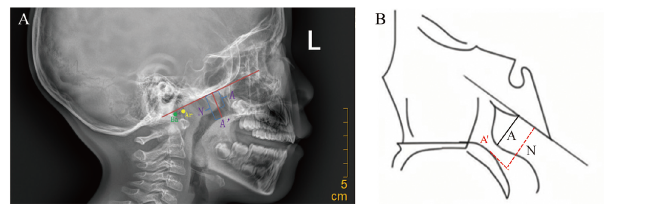

鼻咽侧位X线片通过Fujioka 比率法测量腺样体厚度(A)与鼻咽腔宽度(N)的比值(A/N)[15],在该方法中,需要在鼻咽侧位片上手动标记4个标志点以测量A/N(图1)。然而,这一过程不仅耗时,还高度依赖操作者的个人经验,因此有必要借助更准确高效的算法来自动评估鼻咽侧位片中的腺样体大小。

图1 腺样体厚度/鼻咽腔宽度(A/N)的测量方法及示意图

注:图A为在鼻咽侧位片标记及测量A/N值的方法,图B为其简易示意图,腺样体前缘最凸出点到枕骨斜坡前缘切线的距离为A,A的反向延长线与硬腭后端或软腭前中部上缘的交点(A’)和枕斜面侧面切线之间的垂直距离为N,Ba为颅底点(蝶骨斜坡与枕骨基部的相交顶端),Ar为关节点(下颌髁突颈后缘与颅底下缘交点)。

Figure 1 Measurement method and schematic diagram of adenoid thickness/nasopharynx width(A/N)